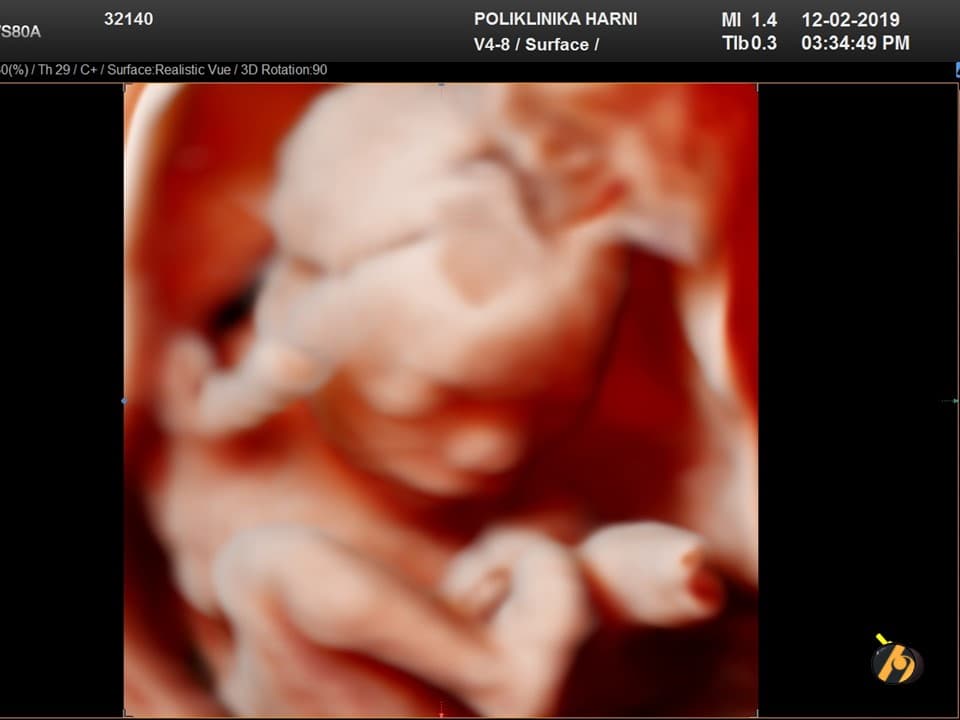

Vaša beba dugačka je sveukupno 20 - 23 cm, teška oko 200 - 250 g i veličnom se uspoređuje s mangom.